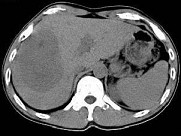

- 单项选择题根据所提供的图像,最可能的诊断是 ( )

A、肝血管瘤

B、FNH

C、肝癌

D、肝腺瘤

E、以上都不是